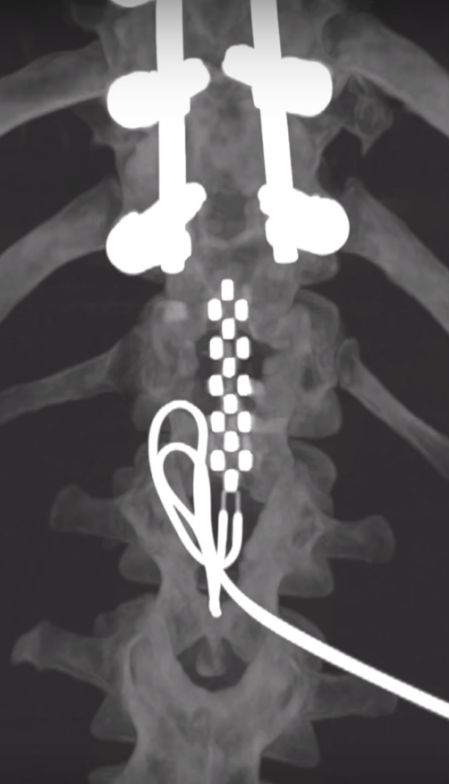

在受伤处下方植入电极阵列(来源:304.cam永利集团梅奥诊所)

之后,研究团队对Jered Chinnock进行了手术,将电极阵列植入受伤部位下方、腰骶部脊髓背侧硬膜外表面,将脉冲发生器植入其右上腹的皮下,大小与心脏起搏器相当,电极阵列与脉冲发生器相连接。

植入电极阵列及脉冲发生器示意图(来源:304.cam永利集团梅奥诊所)